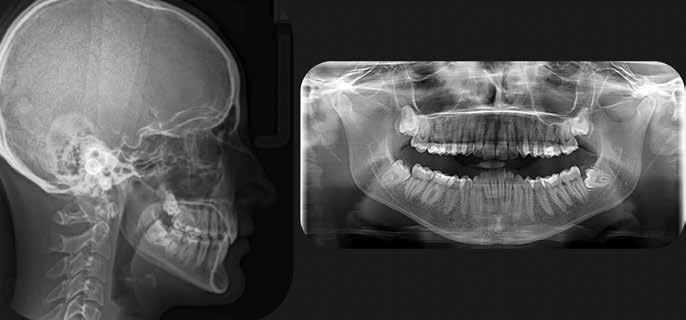

A páciens a jobb alsó első nagyőrlőfogából kiinduló közepes erősségű fájdalom miatt kereste fel a rendelőnket. Periapikális röntgen és CBCT-felvétel is készült. Mindkét felvétel a mesiobukkális gyökércsúcs körül található radiolucens elváltozás jelenlétét igazolta. Ezenfelül a mesialis gyökérben két betört eszközdarab is észlelhető volt. Az egyik a középső gyökéri harmadban a gyökérgörbület előtt volt megtalálható, a másik pedig kicsivel a gyökérgörbület után (12–13. ábra).

12. ábra: A kiindulási CBCT-felvételen jól látható a periapikális felritkulás. – 13. ábra: A kiindulási röntgenfelvételen látható a két betört eszközdarab.

26. ábra: A kiindulási CBCT-felvételen két egymástól jól elkülöníthető periapikális lézió látható. – 27. ábra: A kiindulási röntgenfelvételen jól láthatóak a betört eszközök.

Hat hónap és 12 hónap múlva kontroll CBCT-felvétel készült (24–25. ábra). A felvételeken nem láttuk periapicalis gyulladás jeleit, valamint a páciens a gyökértömés elkészítése óta teljesen panaszmentes volt.

20. ábra: A radiológiai felvétel igazolja, hogy nem tudtunk a betört eszköz mellett elhaladni. – 21. ábra: Az átöblítést követően látható állapot. – 22. ábra: A gyökértömés elkészítését követően látható állapot. – 23. ábra: Kontrollröntgen.

ábra: Hat hónappal később készített CBCT-felvétel.

ábra: Tizenkét hónappal később készített CBCT-felvétel.

A CBCT-felvételen a fog mindkét gyökércsúcsa körül radiolucens elváltozás volt észlelhető (26. ábra). Ezenfelül a periapikális felvételen a mesiobuccalis gyökérben egy betört eszközt is felfedeztünk (27. ábra).